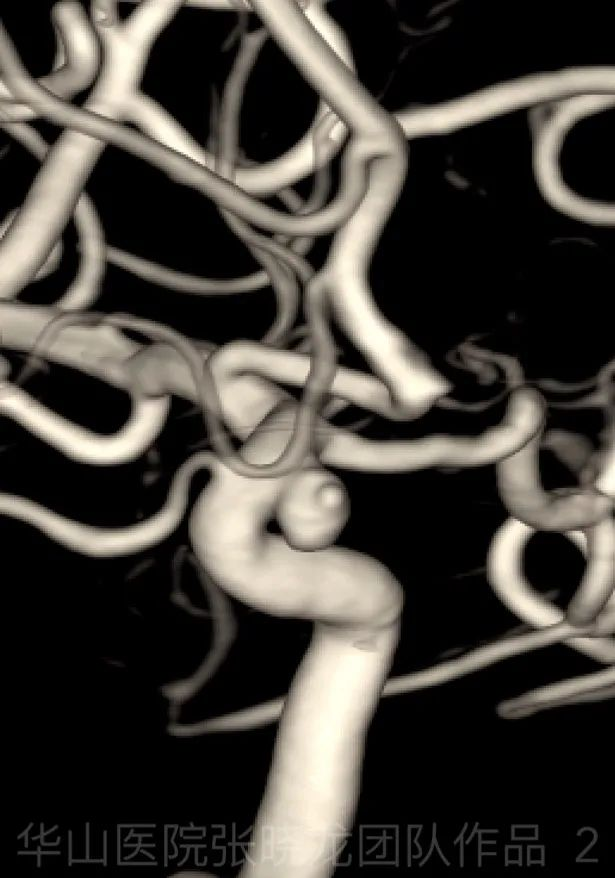

Video 1. Rotational angiography shows an irregular wide neck ophthalmic artery aneurysm with a daughter sac. 视频 1. 旋转血管造影可见一不规则宽颈颈眼动脉动脉瘤伴子瘤。

Figure 1 GIF. Measurement: Aneurysm 3.6mm; Neck 3.67mm; Parent artery 3.49mm. 图 1. 测量:动脉瘤 3.6mm;瘤颈 3.67mm;载瘤动脉 3.49mm。